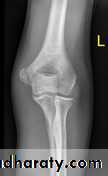

Supracondylar fracture of humerus:

Supracondylar humeral fracture in children is one of the most common fractures seen in the pediatric orthopedic clinic setting worldwide. It's a fracture that occurs at the supracondylar area or the metaphysis of the distal humerus & accounts for 65.4% of upper extremity fractures in children .There are two types of supracondylar fractures in children according to direction of displacement of distal fragment i.e. extension type (97%) and flexion (3%).X-ray of elbow joint (lat. View)

The fracture can however be difficult to identify and often a joint effusion is used to increase one's suspicion of the presence of a fracture. Upon examination the doctor will evaluate the arm for signs of damage to the nerves and blood vessels; they will look for swelling and deformity. This will allow the doctor to determine a likely diagnosis. Damage to the elbow is a common injury in children; injuries to blood supply of the arm may necessitate early surgical intervention. The radiographic study of the injured limb should include an anteroposterior (AP) and a lateral view.(AP) –view ( Lat.) –view